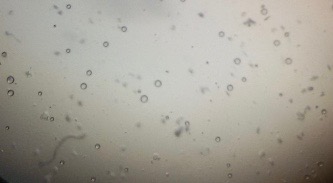

Preparation of niosomes from proniosomes and morphological evaluation (Photomicroscopy)

The optical photographs of all reconstituted proniosomal formulae are shown in fig. (1-28). The photographs revealed that the formed niosomes are unilamellar vesicles with a spherical shape and smooth surface. The vesicles were insular and separate without aggregation or lumping. Apparently, proniosomal formulae containing span 40 and span 60 yielded vesicles of large numbers with well-identified outline and core which will affect the entrapment efficiency of loaded drug directly. However proniosomal formulae containing span 20 and span 80 produced small numbers of vesicles with a slightly different outline. This may be due to the high phase transition temperatures of both span 40 and span 60 which will cause the formation of a large number of stable niosomal vesicles. The phase transition temperatures for span 20, 40 and 60 are 16, 42 and 53 °C; respectively, however, span 80 possess the lowest phase transition temperature at 12 °C [35]. This explains why proniosomal formulae containing span 20 and span 80 produce small numbers of vesicles upon hydration.